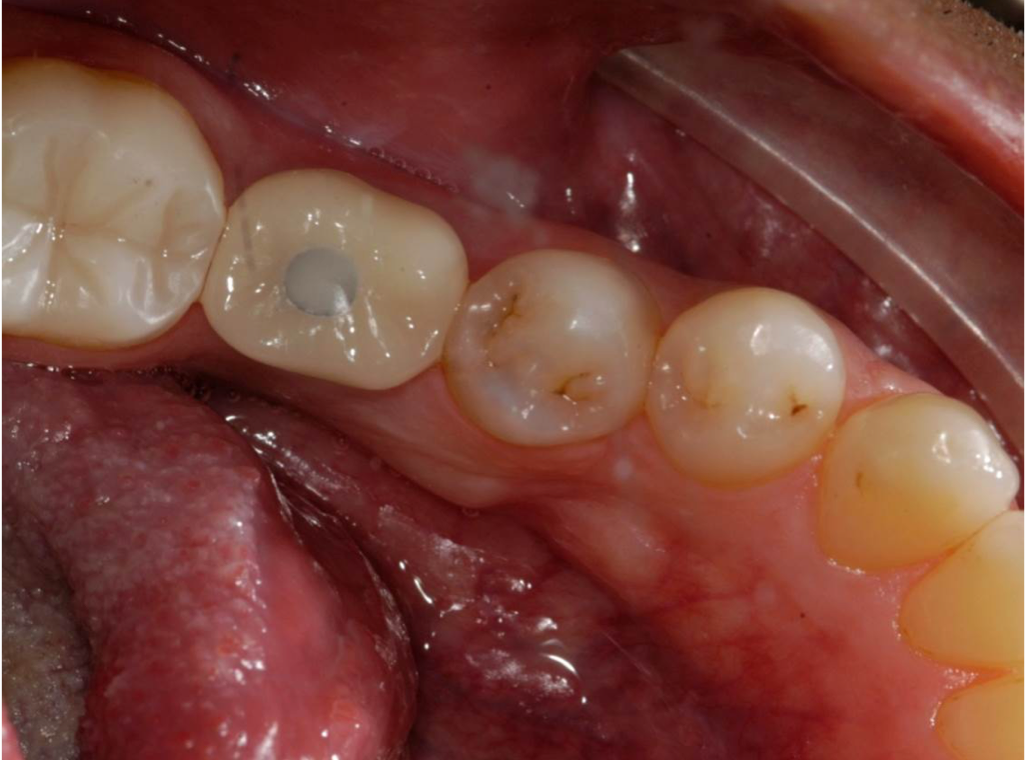

Fig 2. If the distance is less than 7 mm, an unsightly gray dot may result.

Figure 2

The author teaches "restorative address 73-422," a metaphorical street address, as the best method to help navigate an implant start to finish, where each number corresponds to a significant measurement. These measurements can be viewed by looking at the cross-section of a cone-beam computed tomography (CBCT) scan. The first number in the address, "7," represents the distance that the restorative platform should be from the desired occlusal table (Figure 1). An abutment 5 mm in length will minimize the chances of the restoration dislodging from the abutment. Then, above coronal to the abutment, there should be 2 mm of restorative material to ensure a strong restoration that will not fracture or break. Together, the abutment length of 5 mm plus the 2 mm of restorative material equals 7 mm. If the distance between the restorative platform of the implant abutment and the desired occlusal table is less than 7 mm, it will be difficult to mask out the screw-access hole and may result in an unsightly gray dot in the middle of the implant restoration (Figure 2). If the distance is slightly greater than 7 mm, that is acceptable, but it should not be less.